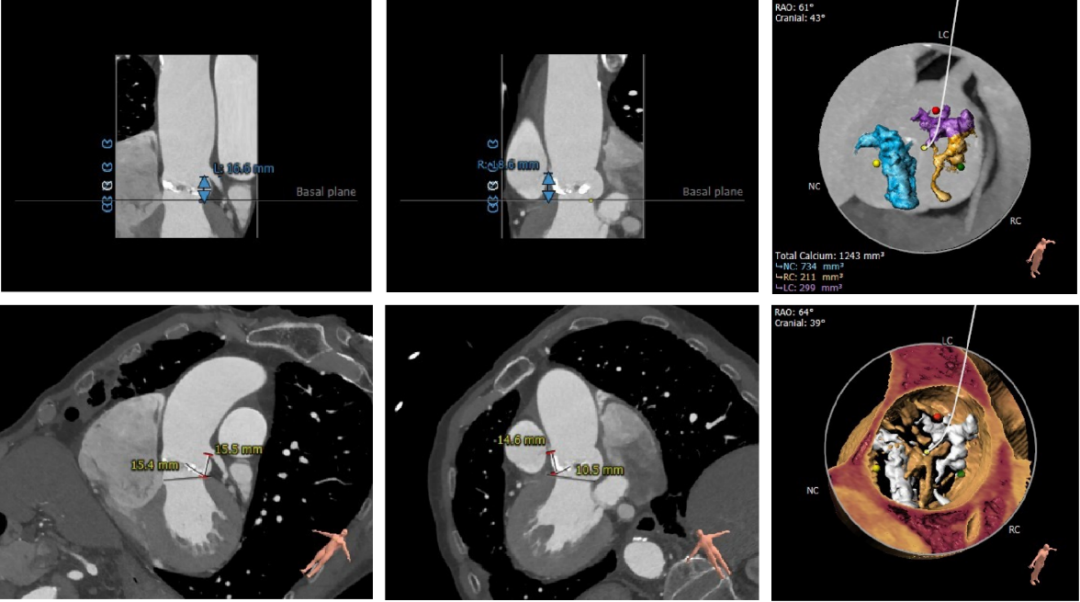

主动脉根部测量

瓣上结构测量与分析

冠脉阻挡风险及钙化评估

外周血管入路评估